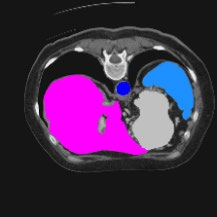

Transformers have made remarkable progress towards modeling long-range dependencies within the medical image analysis domain. However, current transformer-based models suffer from several disadvantages: (1) existing methods fail to capture the important features of the images due to the naive tokenization scheme; (2) the models suffer from information loss because they only consider single-scale feature representations; and (3) the segmentation label maps generated by the models are not accurate enough without considering rich semantic contexts and anatomical textures. In this work, we present CASTformer, a novel type of generative adversarial transformers, for 2D medical image segmentation. First, we take advantage of the pyramid structure to construct multi-scale representations and handle multi-scale variations. We then design a novel class-aware transformer module to better learn the discriminative regions of objects with semantic structures. Lastly, we utilize an adversarial training strategy that boosts segmentation accuracy and correspondingly allows a transformer-based discriminator to capture high-level semantically correlated contents and low-level anatomical features. Our experiments demonstrate that CASTformer dramatically outperforms previous state-of-the-art transformer-based approaches on three benchmarks, obtaining 2.54%-5.88% absolute improvements in Dice over previous models. Further qualitative experiments provide a more detailed picture of the model's inner workings, shed light on the challenges in improved transparency, and demonstrate that transfer learning can greatly improve performance and reduce the size of medical image datasets in training, making CASTformer a strong starting point for downstream medical image analysis tasks.